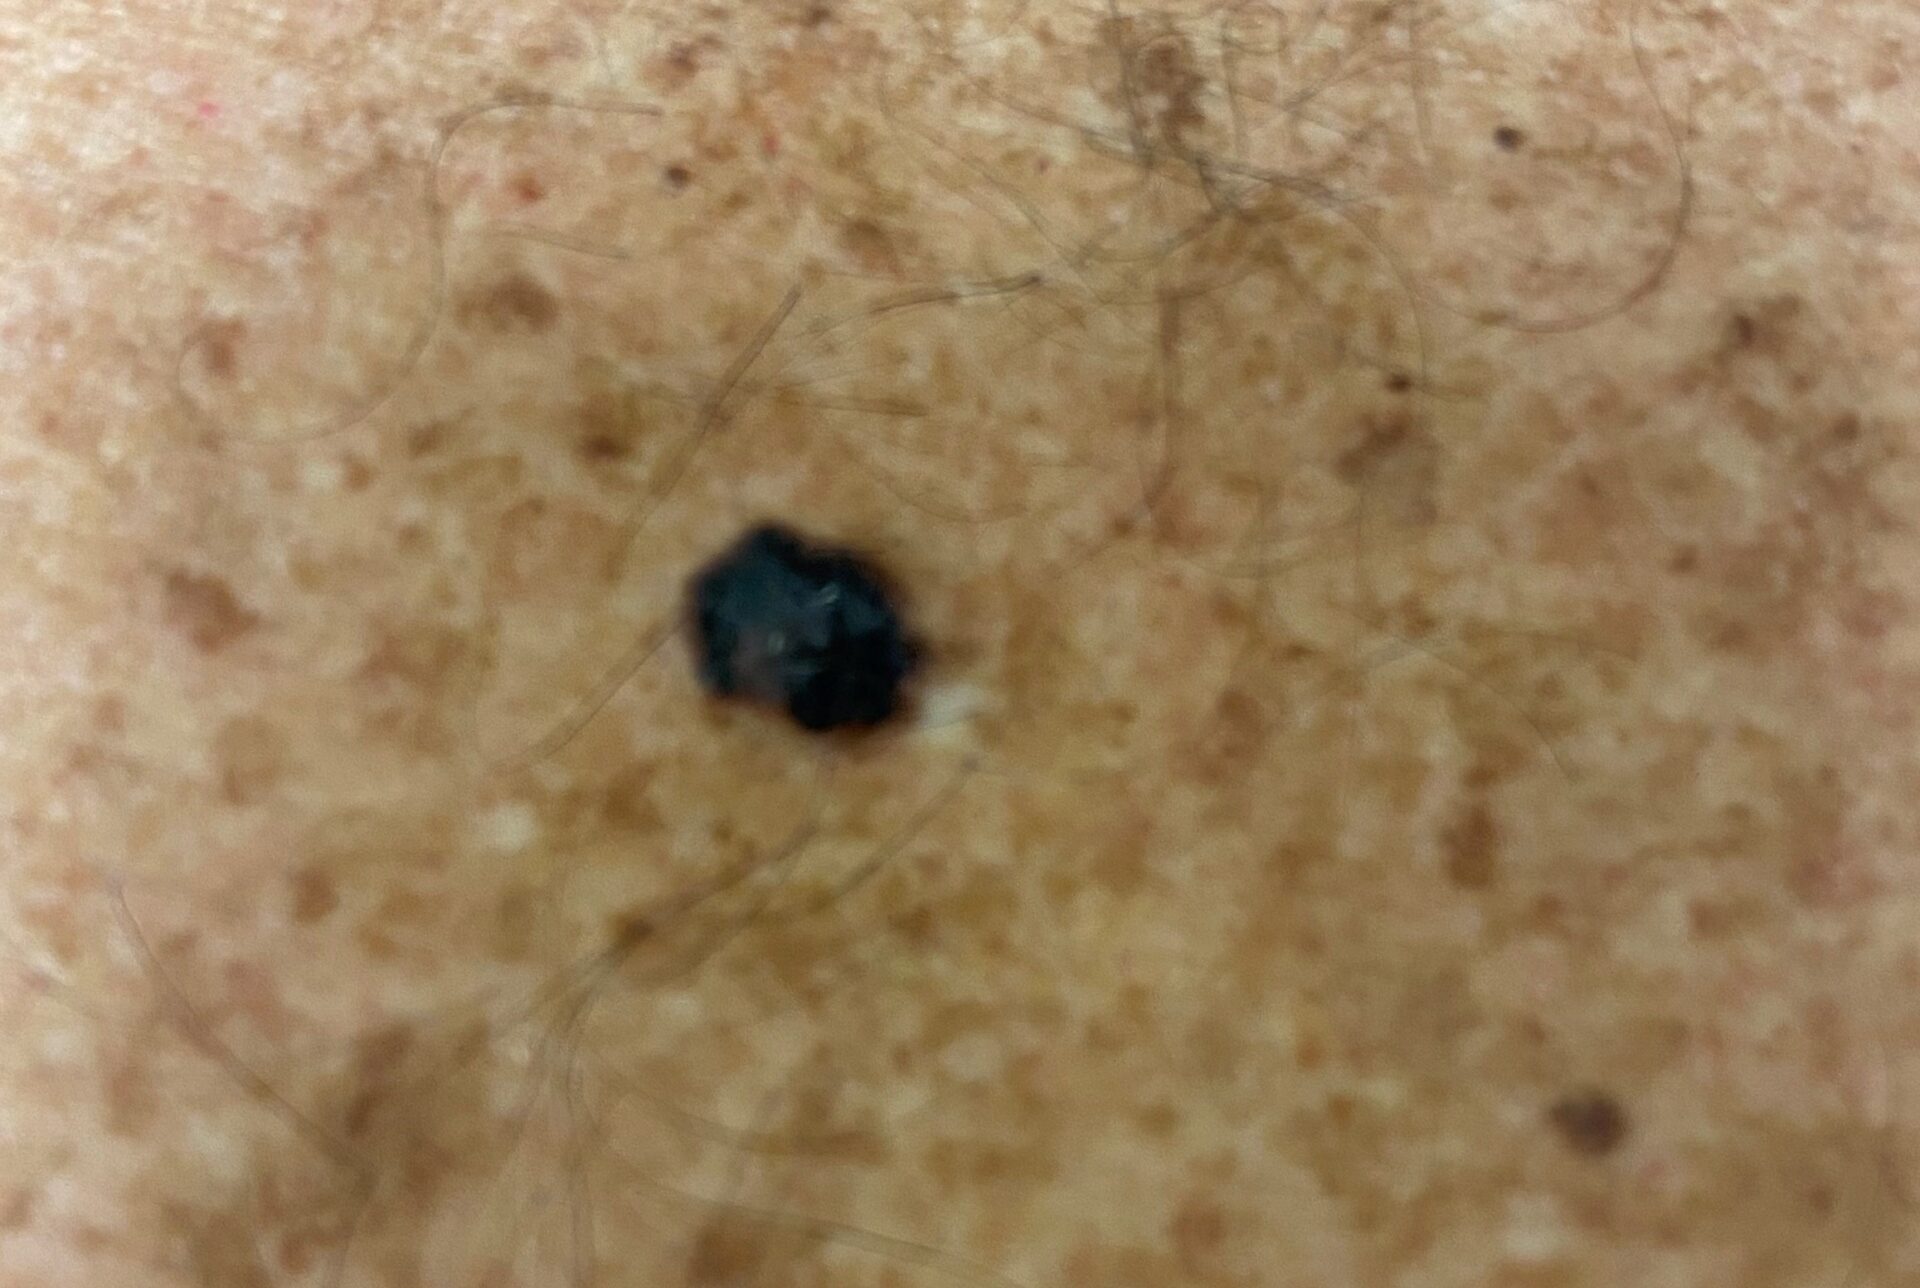

Nodular melanoma on the leg of a Native American woman.

Photo: International Skin Imaging Collaboration